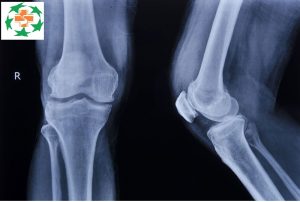

Chụp X-quang là một kiểm tra phổ biến trong y học, dùng tia X phát ra từ máy X-quang xuyên qua các mô và các thành phần dịch trong cơ thể, để xây dựng và tái tạo lại hình ảnh cấu trúc bộ phận bên trong cơ thể, hỗ trợ cho quá trình chẩn đoán bệnh của bác sĩ.

- Các mô đặc, cứng như xương: khi chụp sẽ cản trở tia X nên sẽ cho ra hình ảnh trắng;

- Các mô cơ, tạng, mô mềm: có ít tia X xuyên qua nên hình ảnh chụp được thường màu xám;

- Các mô chứa không khí, nước: tia X xuyên qua nhiều nên thường sẽ có màu đen.